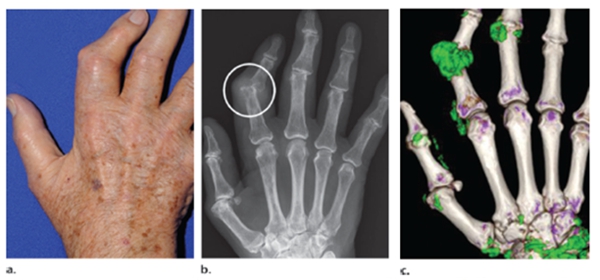

我繼續(xù)說:“而且,你看看你的化驗(yàn)單,尿酸正常的上限是420μmol/L。為什么設(shè)定這樣一個(gè)數(shù)字呢?打個(gè)比喻,你身體里的血液就像一杯水,往水里放一兩勺鹽,是不會(huì)產(chǎn)生沉淀的。但是,如果你放十幾勺鹽進(jìn)去,也就是說尿酸超過420μmol/L,就會(huì)產(chǎn)生尿酸鹽,并在血管以外的地方沉淀。這些沉淀下來的尿酸要比血液中的多很多,而抽血是無法計(jì)算出來的只能通過CT檢查來發(fā)現(xiàn)?!?/span>

如圖所示圖,a是肉眼看到的手,圖b是X光拍攝到的影像,而圖c中的綠色物質(zhì)就是尿酸鹽,通過CT可以計(jì)算出沉淀在血管外的尿酸鹽,且可以判斷痛風(fēng)的治療效果。

對(duì)于痛風(fēng)患者,要清除血管里的尿酸,以及血管外沉淀的尿酸,藥不能停,服藥后還要定期復(fù)查,讓身體里的血尿酸長(zhǎng)期保持在平穩(wěn)狀態(tài)。只有長(zhǎng)期將血液里的尿酸降低沉淀下來的尿酸才會(huì)減少,這樣,痛風(fēng)才不會(huì)發(fā)作,盡可能地保護(hù)我們的關(guān)節(jié)、血管、心臟、大腦和腎臟。